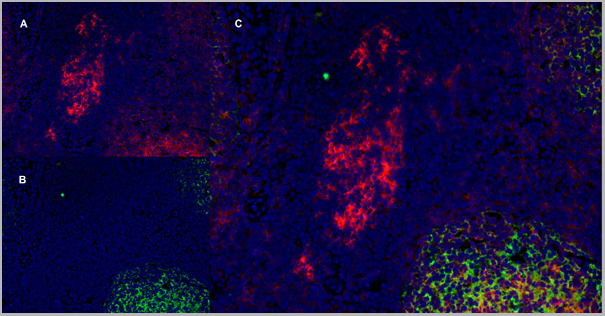

Application Data

(Immunofluorescence staining of a human tonsil cryostetion with Mouse anti Human CD40 antibody, clone LOB7/6 , red in A and Mouse anti Human CD21 antibody, clone LB21 , green in B. The merged image is C with nuclei counterstained blue using DAPI. Medium power)